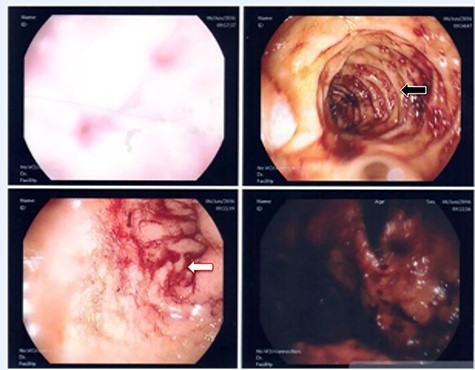

A 36-year-old male, involved in a minor motor vehicle accident while driving his car. He lost consciousness following a sudden onset of transient loss of vision which was not associated with palpitation or dizziness. His previous medical history revealed arterial hypertension and a corrected aortic coarctation with interposition graft at the age of 14. Pan CT scan was unremarkable except for thickening of the desending throacic aorta. His white blood count was very high (68 000 per cubic millimeter of blood). One day after the car accident, he developed nausea, hematemesis and melana. Upper GI endoscopy revealed blood in the stomach and distal esophafgus with no identifiable source of bleeding (Fig. 6). The patient developed massive hematemsis with hypotension requiring intubation and resuscitation. Another CT scan showed air pocket around distal aorta and contrast extravasation to the esophagus (Fig. 7). Another endoscopy revealed distal esophageal ulcer with clot extending toward the stomach (Fig. 8). AEF was suspected and then confirmed by aortogram. The fistula was treated by TEVAR (20 mm × 11.5 cm Valiant covered stent - Medtronic company, USA) followed by fully covered esophageal stent in the middle of the esophagus (Fig. 9).

First upper endoscopy blood within the stomach and duodenum; the esophagus image was not clear and no active bleed can be seen.

(A) CT study with contrast showing gas adjacent to the descending thoracic aorta with thickened soft tissue around the esophagus. (B) Vascular contrast within the esophagus and projecting outside the aorta forming ‘pseudoaneurysm’ or penetrating aortic ulcer.

Second upper endoscopy fresh bleeding from the distal esophagus and after washing the blood an adherent clot extending from an ulcer going down into the stomach can be seen.